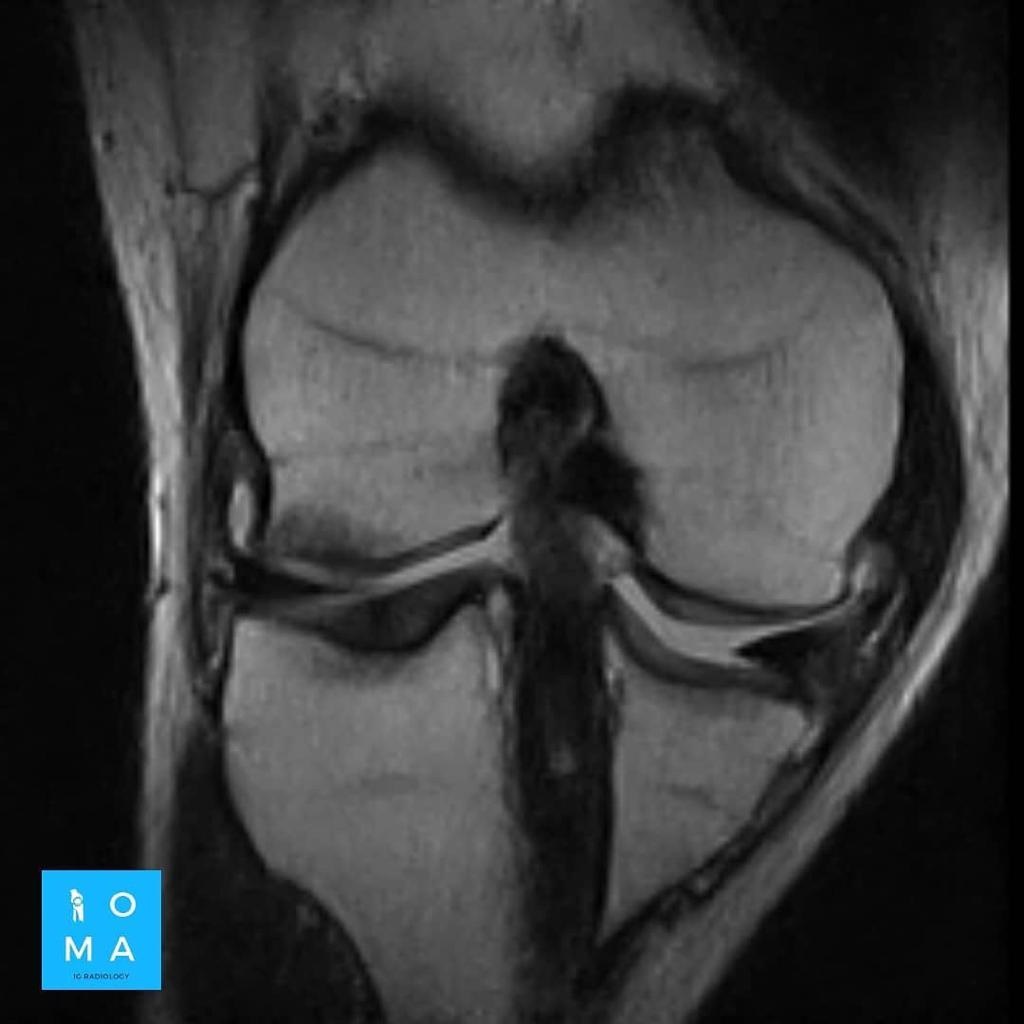

La evaluación hepatica entre Adenoma y HNF por resonancia magnética y su diferenciación con hepatocarcinoma puede ser difícil en ciertos casos aún, con el uso de contraste hepato especifico.

Se presenta caso de paciente de la 3a década, que en su embarazo se diagnostica con sospecha de adenoma y posterior al embarazo se realiza estudio de control contrastado para su mejor diferenciación.

En la evaluación con medio de contraste, se evalúa la relación arterial y de las venas, esto puede servir para buscar la arteria central relacionada con la hiperplasia nodular focal o bien, para evaluar la relación con las estructuras vasculares que son muy importantes para el planeamiento quirúrgico .

en este caso, aún cuando los hallazgos son atípicos tanto para hiperplasia nodular focal como para adenoma, nos inclinamos hacia el diagnóstico de adenoma debido a los antecedentes de la paciente, el tamaño de la lesión, el área de sangrado, el contenido de grasa.